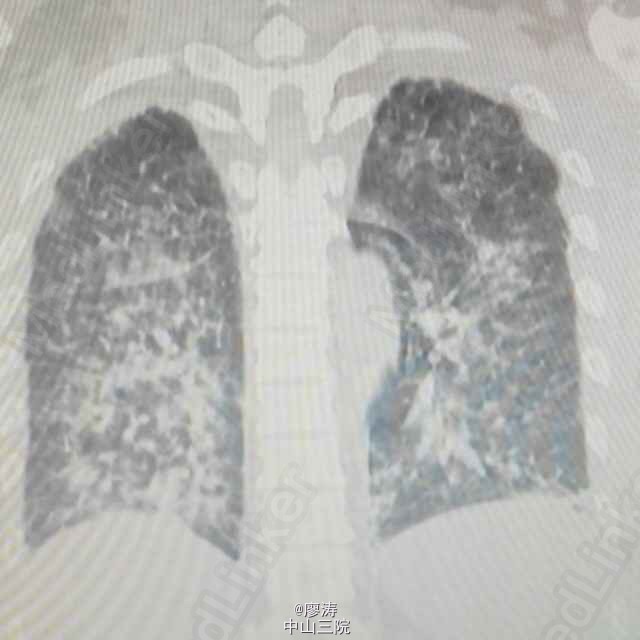

患者肾移植术后3月余,发热6小时入院,CT检查双肺弥漫性实变,呈“毛玻璃状”,CMV抗体检查阳性,诊断为巨细胞病毒性肺炎。给予抗病毒、抗细菌和吸氧等辅助治疗。肾移植术后服用免疫抑制剂,抵抗力降低,容易发生机会性感染。其中最严重死亡率最高的就是巨细胞病毒感染(CMV),死亡率高达60%以上,好发于肾移植术后三周左右。